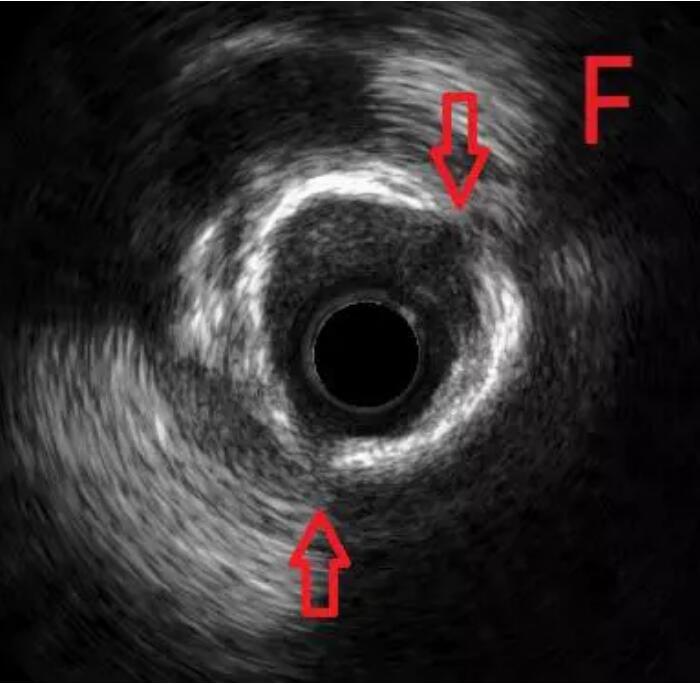

通过对该病变的分析,杨巍主任决定采用“振波球囊”对病变进行预处理。将振波球囊送至环形钙化处并启动4次,随后再次使用预扩球囊对病变处进行扩张,显示可以充分扩张(图E),继续IVUS检查,证实钙化斑块已经裂开(图F)。